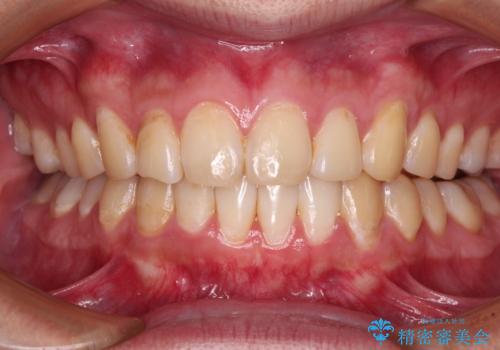

- 下顎前歯が欠損しており、前歯がデコボコとなっている歯並びを気にして来院された患者様です。

下顎の左右側切歯2本が欠損しており、上顎歯列がデコボコとなっている状態でした。

下顎歯列に対して上顎歯列が相対的に大きくなっているため、デコボコとなっているだけでなく、下顎前歯が見えなくなるくらいのディープバイトにもなっていました。